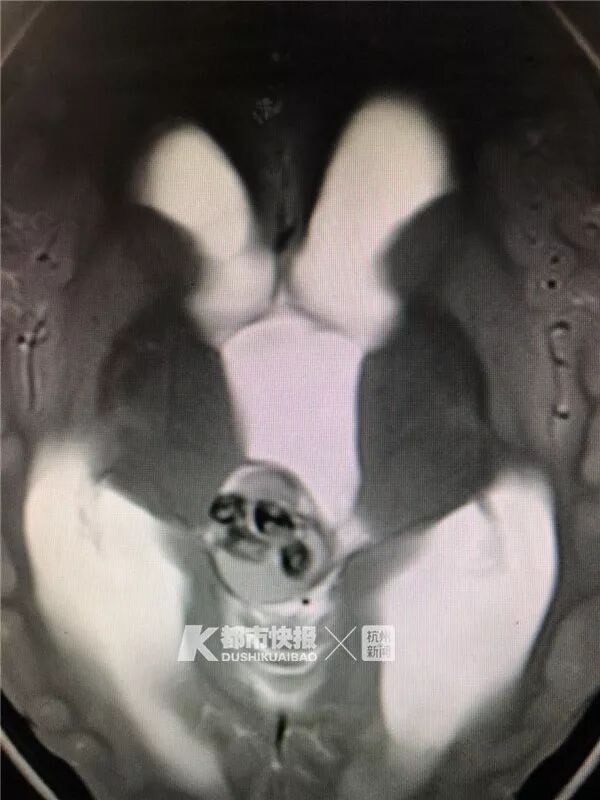

沈医师看了小刚的CT检查单,再结合之前有头痛、呕吐等症状,让小刚再做一个核磁共振检查来明确诊断。检查发现,小刚的脑积水明显增多,正常5岁孩子的脑室宽度大约在3毫米左右,而小刚的脑室宽度达到了18毫米。更奇怪的是,颅内正中的那个高密度包块,呈一颗颗的颗粒状物质,密度非常高。

根据这些检查结果,沈医师判断小刚的颅内包块可能是骨骼性质的问题。经过评估后,决定手术治疗。

手术时发现,小刚颅内包块里那些一颗颗的物质,竟然是一颗颗牙齿,一共有9颗!除此之外,包块里还有少量头发、皮脂、骨头等组织。